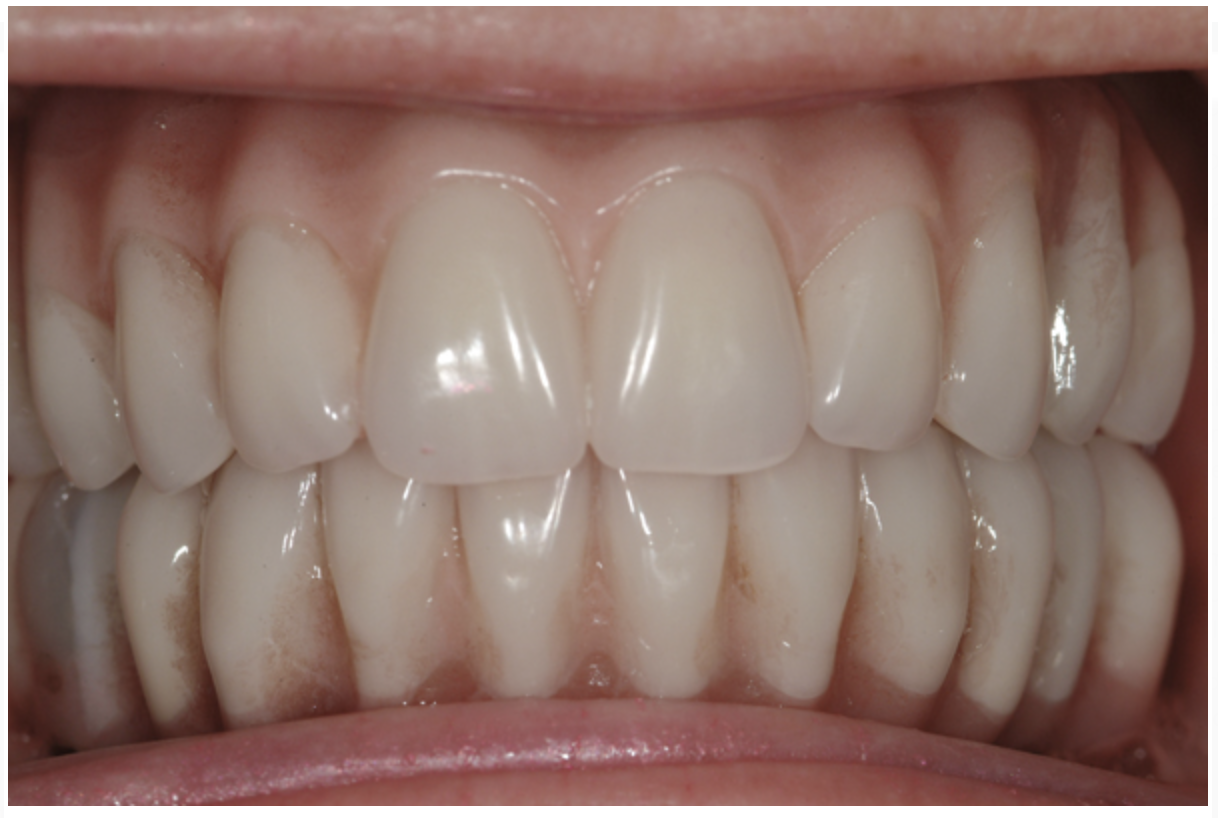

Fig 20. Patient intraoral condition 3 years following delivery of maxillary and mandibular All-on-4 definitive prosthesis.

Figure 20